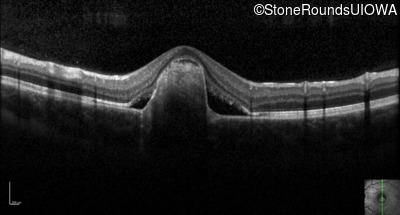

Optical Coherence Tomography - Right - 20/40 -1 sc

Exemplar / OCT Stack

OCT Stack